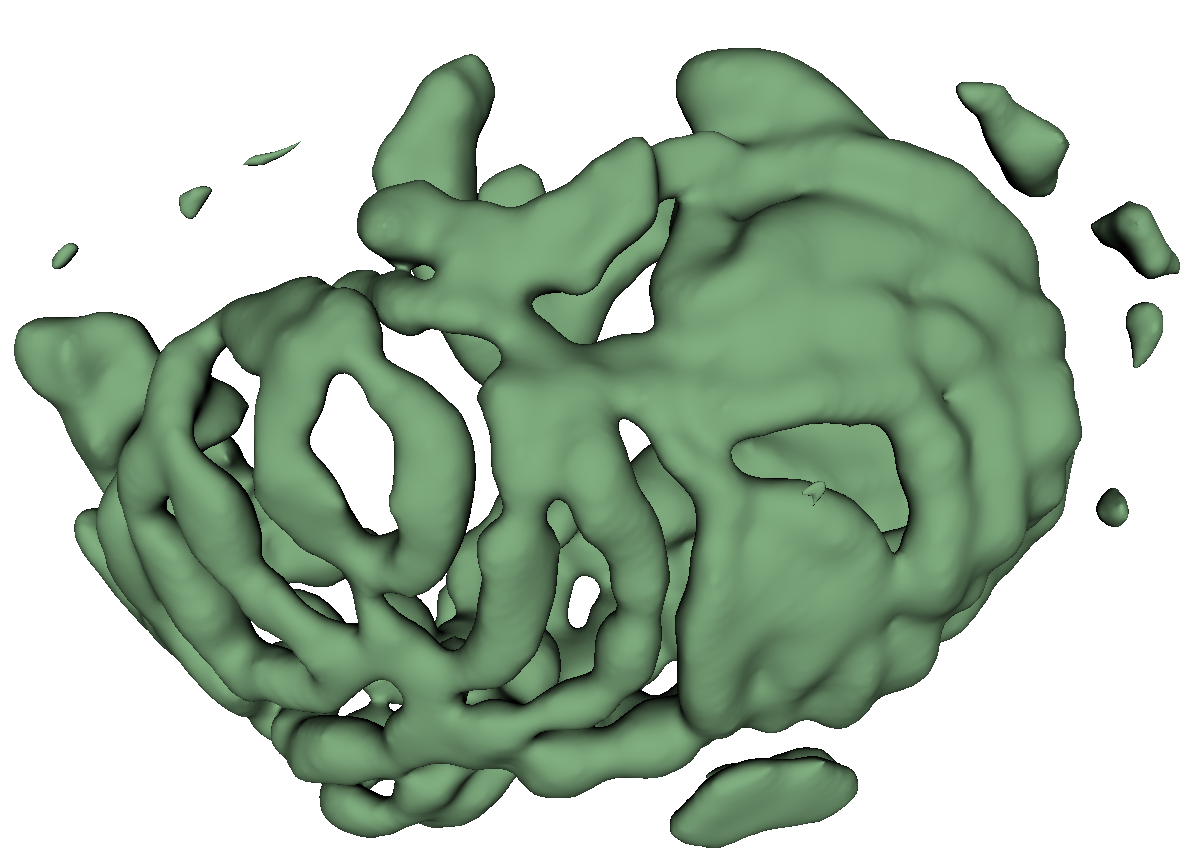

Fig. 3 shows example segmentation results. The proposed method eliminates false positives on the large bowel by the help of the applied topological constraint. Fig. 4 further clarifies the effectiveness of the proposed method by presenting 3D rendered segmentations. The proposed method produces a more topologically correct segmentation of the small bowel with fewer false positives. Fig. 5 presents example barcode diagrams, which again show the reduced numbers of connected components and holes within the segmentation result of the proposed method.

A

B

C

D